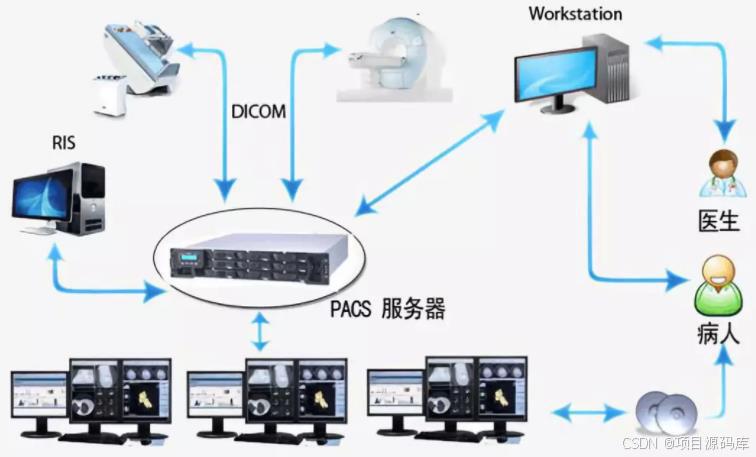

PACS系统即医学影像存档与通信系统,是医疗领域中不可或缺的信息技术系统。它主要负责医院内医学影像的数字化存储、管理、传输和显示,极大地促进了医疗影像信息的高效利用和共享。它可以集成多种医疗设备,如 CT、MR、CR、超声、视频采集、X 光机、 心血管机、核医学等,将这些设备产生的数字影像转换成标准格式,进行存储和管理,以便医生和专业技术人员进行诊断和治疗。

PACS系统通常由以下几个关键部分组成:

影像设备:如CT、MRI、X光机、超声设备等,用于生成医学影像。

影像采集器:确保从这些设备中提取的影像转换为标准的DICOM格式。

存储系统:包括在线存储和长期归档存储,用于保存大量影像数据。

传输系统:利用网络技术,确保影像在医院内部或远程位置的快速传输。

影像工作站:医生使用的工作站,支持查看、分析和处理影像。

数据库服务器:存储相关的患者信息和影像元数据。

PACS系统与HIS(医院信息系统)和RIS(放射信息系统)紧密集成,业务流程大致如下:

1. 临床医生通过HIS系统开具电子检查单。

2. RIS系统进行预约、审核和费用确认。

3. PACS与RIS通过HL7消息交换信息,调度检查。

4. 检查完成后,影像以DICOM格式发送到PACS系统。

5. 影像经过质量控制后存储,并可被授权用户快速调阅。